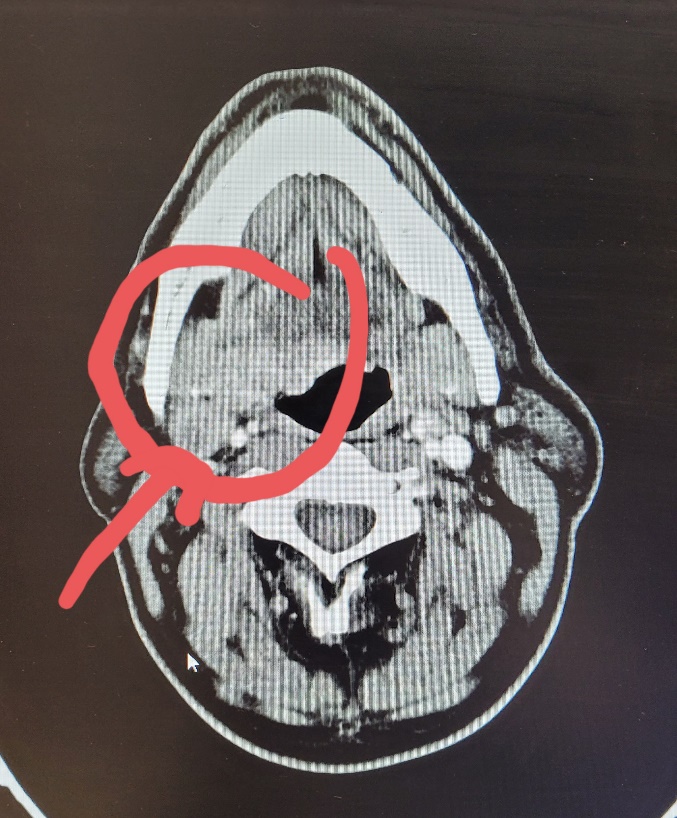

In urma rezultatului, pacientul a fost evaluat de catre membrii comisiei oncologice si indrumat catre dr. TENT PAUL ANDREI in vederea evaluarii oportunitatii unei interventii chirurgicale curative. In urma examenului clinic si imagistic (Fig. 1) pacientul este declarat operabil.

Fig.1 Se observa pe imagine Computer Tomograf cu substanta de contrast, secțiune axiala, formatiunea tumorala (incercuita) si un ganglion sugestiv metastatic jugulo-carotidian superior drept (indicat de sageata).